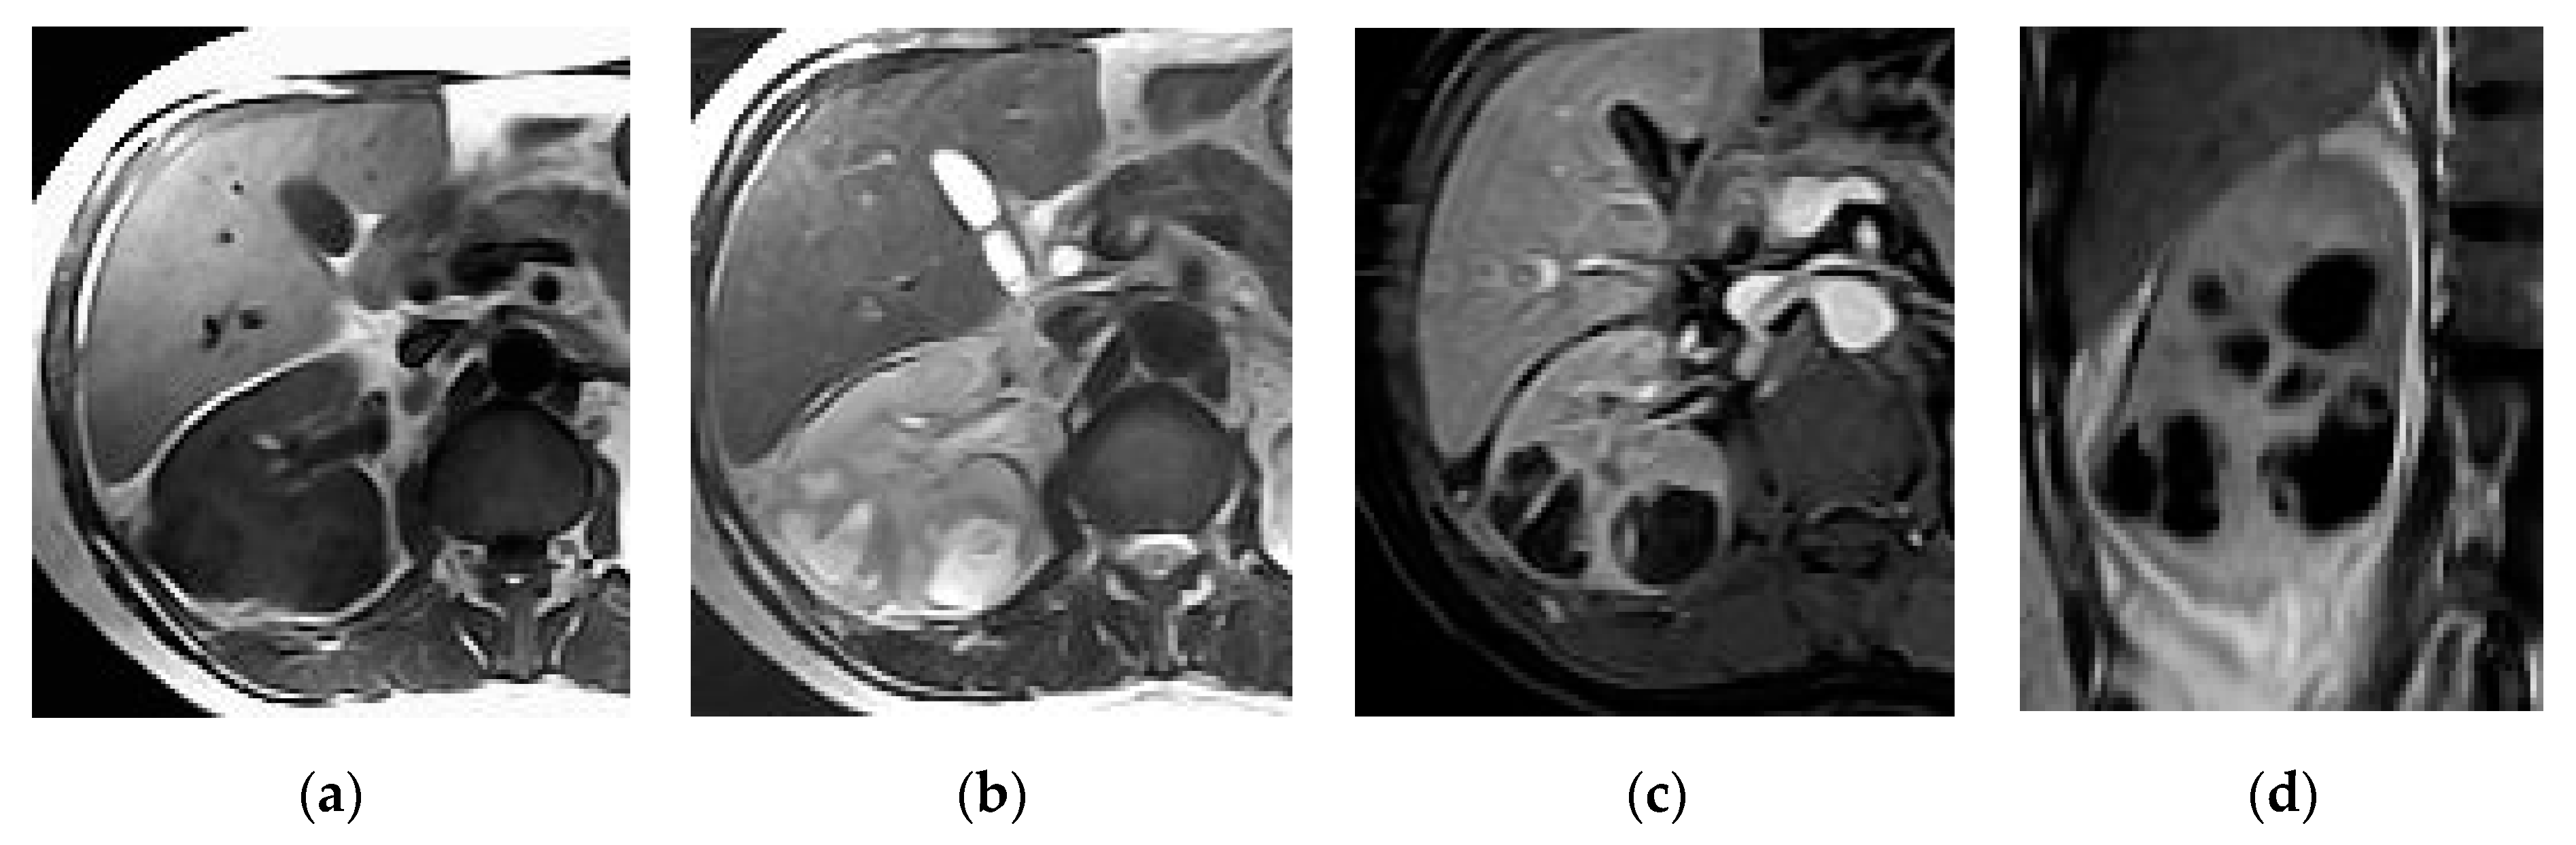

2.3. Pyonephrosis

| Pyonephrosis | Dilated thick-walled hyperenhancing collecting system, distended with high attenuation pus-filled fluid, fluid—fluid layering at T2WI, and thinning of the renal cortex. |